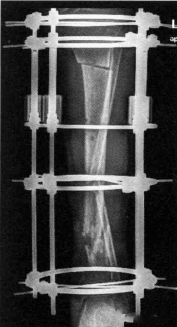

(环式外固定器外观)

肢体延长与关节切除融合的骨外固定,对其稳定性要求则是主要的,否则难以避免由于固定刚度不足所造成的许多并发症。因此,必须根据治疗需要选择力学性能合适的外固定器。